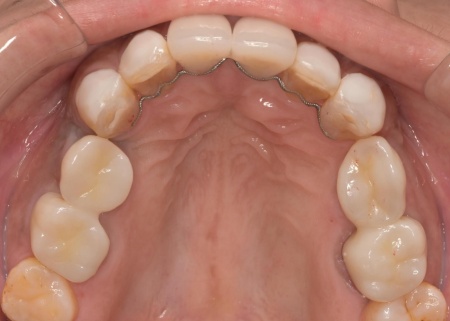

上顎の前歯2本ずつと奥歯4本(左右中切歯・第2小臼歯・第1大臼歯)、下顎の奥歯7本(左第1小臼歯・左右第2小臼歯・第1大臼歯・第2大臼歯)には、見た目が自然なセラミックの被せ物「ジルコニアクラウン」を装着しました。

加えて、上前歯4本(左右側切歯・犬歯)と下前歯5本(左右中切歯・側切歯・右下犬歯)は、ダイレクトクラウンによる修復を行いました。

ダイレクトクラウンとは、レジン(樹脂)を用いて直接歯の形を作り上げていく治療方法です。

歯を削る量が少ない、色や形を細かく調整しながら仕上げられる、治療後は必要に応じて微調整がしやすいなどのメリットがあります。

最後に、見た目や噛み合わせに問題がないかを確認し、治療を終了しました。